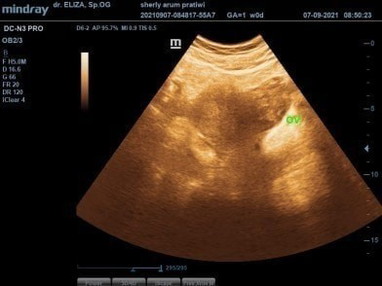

Assalamualaikum bunda, Aku mau sharing siapa tau nih ada yg samaan kaya aku, Aku terakhir mens 11 mei 2021, Bulan juni,juli,agustus aku tespek hasilnya negativ,, Lalu bulan september awal aku tespek alhamdulillah positif tapi ditanggal 3,4,5 masih samar blm terlalu jelas Lalu ditanggal 7 aku usg untuk melihat lebih jelasnya, karna dokter masih ragu sebab ada kaya gumpalan darah kata dokter masih blm tau ini darah yg numpuk karena aku udah 3 bulan gak mens, apa emng bakalan jadi calon janin, Lalu dokter memberitahu aku untuk tespek ulang, alhamdulillah tetep garis 2, dan tambah jelas ya meskipun blm sejelas yg atas nya tapi seengaknya ngebuat aku positif thingking , lalu bidan bilang perkiraan masih 1 bulan Aku dikash obat namanya microgest selain untuk memperkuat kandungan ia juga untuk membantu pertumbuhan janin, Doakan ya bunda semoga kehamilan aku baik baik saja sampai persalinan nanti dan sehat 2" nya.. Penantian 3 tahun 😥 #bantusharing #firstbaby